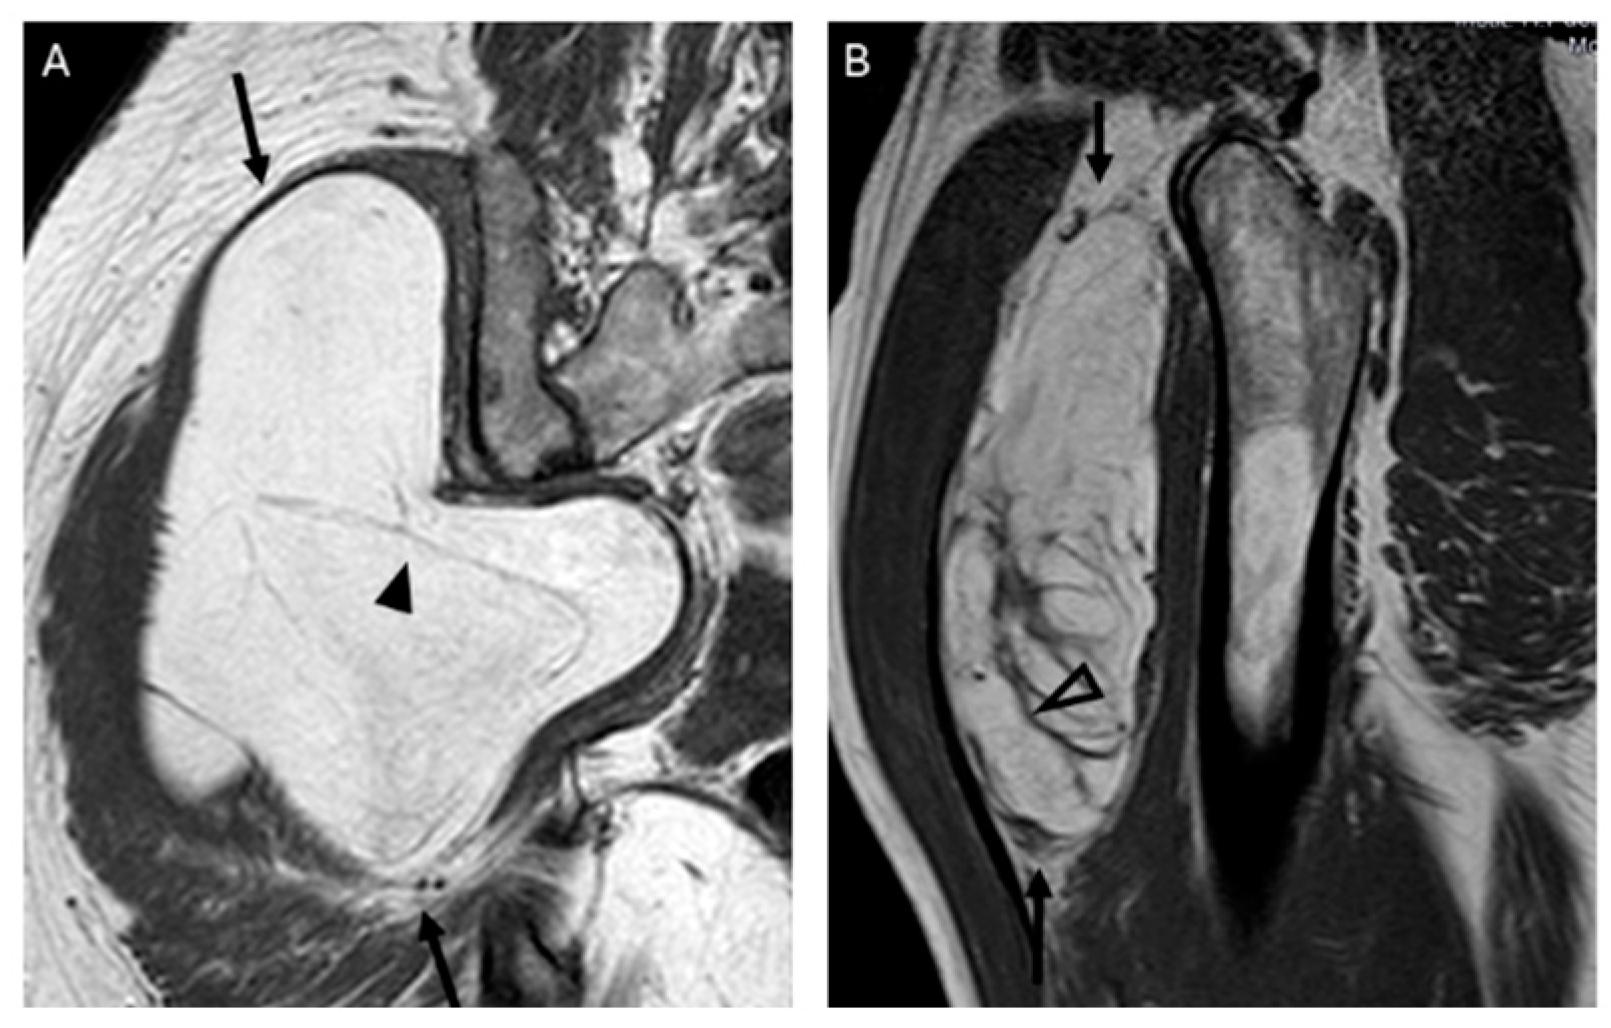

We propose the following approach for managing deep fatty soft tissue tumors based on their MRI characteristics, as illustrated in Figure 3. When a fatty tumor demonstrates homogeneous fat signal intensity, lacks septa and non-fat nodules, and has a maximum dimension of less than 8 cm, it is most likely a lipoma. Conversely, when a deep fatty tumor exhibits septa ≥ 2 mm, more than one non-fat nodule, and a maximum dimension greater than 12.8 cm, it is most likely an ALT. Additionally, if MRI reveals a fatty soft tissue tumor with heterogeneous signal intensity, septa < 2 mm, or a single non-fat nodule—regardless of the tumor’s maximum size—a biopsy with MDM2 determination is required to characterize the tumor before initiating treatment.

The presence and thickness of septa show significant differences between lipomas and ALTs. This one agrees with the findings of Kransdorf and Hosono, where the septa were thick and irregular in ALT/WDL and thin in lipoma [12,16]. Similarly, Brisson observed that lipomas were isointense to subcutaneous fat and may contain a few thin septa [17]. In our series, the absence of septa indicates lipoma and septa ≥ 2 mm is suggested of ALT. Septa < 2 mm can be indicative of either lipoma or ALTs (Figure 5).

There was typically more than one non-fat nodule in ALT, while lipomas usually had only one (Figure 6). Unlike other studies, which suggested that non-fat nodules larger than 1 cm in diameter are an important discriminator favoring ALT over lipoma [17], our findings did not support this distinction.

Figure 5. Septations. Coronal T1W image (A) showing a lipomatous tumor (black arrows) with thin septa < 2 mm (arrowhead) in the gluteal region. Final diagnosis: lipoma (MDM2 negative). Sagittal T1W image (B) showing a lipomatous tumor (black arrows) with thick septa ≥ 2 mm (open arrowhead). Final diagnosis: atypical lipomatous tumor (MDM2 positive).